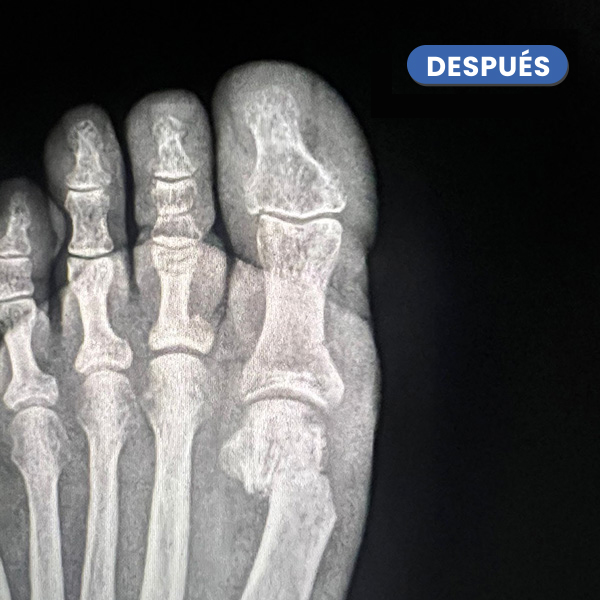

La Radiografía presenta el antes y el después a los 20 días del control radiológico tras la cura. Se aprecia la evolución en la consolidación ósea y la corrección de la articulación del hallux.